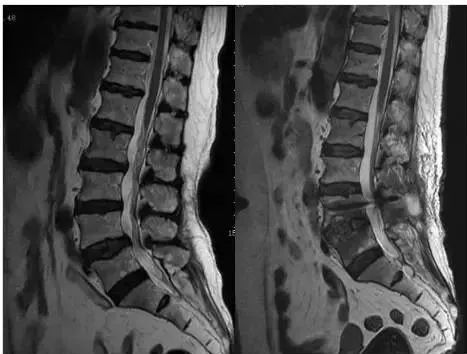

男性,70 岁,间歇性跛行 3 年,加重半年,腰椎马尾神经冗余的 MRI 表现

左图:MRI 横断面 T2WI 图像显示 L3~L4 椎管严重狭窄,黄韧带肥厚,椎间盘膨出;

右图:MRI 矢状位 T2WI 图像,腰 3/4 椎间隙水平以上,马尾神经迂曲缠绕,表现出典型的冗余现象

女性,74 岁,腰痛伴间歇性跛行 2 年余,腰椎管狭窄症患者手术前后马尾神经的 MRI 表现

左图:MRI 矢状位 T2WI 图像显示 L4 椎体退行性滑脱,椎管狭窄,L4~L5 间隙水平以上马尾神经迂曲,表现为冗余现象;

右图:MRI 矢状位 T2WI 图像显示 L4-5 椎管扩大减压术后,马尾神经冗余现象消失